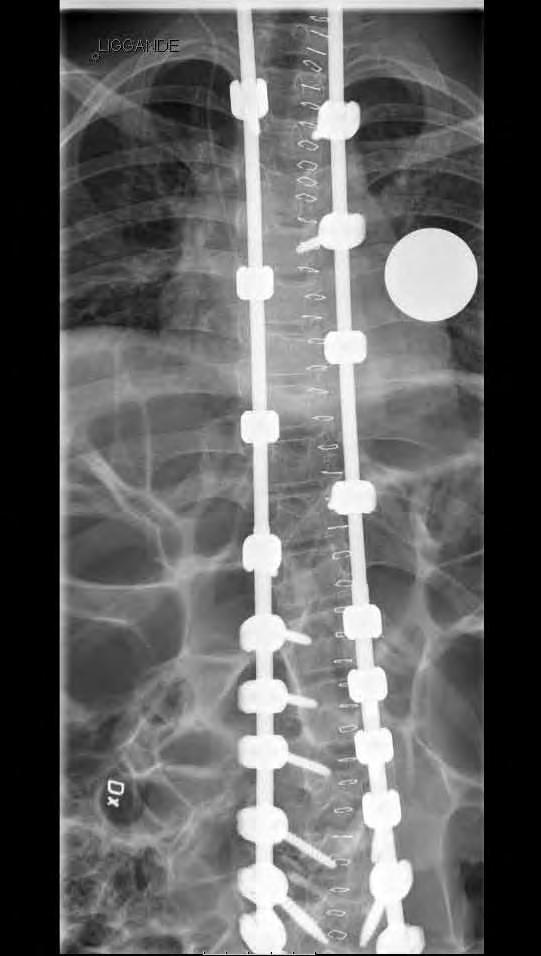

12 årig flicka med CP. Hon hade fått en starkt försämrad sittställning på grund av progressiv lumbal skolios. vid opererationen användes bakre teknik för att först få korrektion av den lumbala skoliosen. Operationen extenderades ovan Th12 med tunnare stag som är längre än nödvändigt vid operationstillfället. Syftet var att man med denna konstruktion (Shilla-teknik) har stag som ska kunna glida i skruvhuvudena i bröstryggen, allt för att kunna få thorax att växa ytterligare. I thorakalryggen infördes skruvarna transmuskulärt med hjälp av navigationsutrustning för att inte stimulera till bakre fusion.

Postop PA av ländrygg och nedre bröstrygg visande en god korrektion av skoliosen.

CT-lågdos med axialt snitt L3 preop visande 18 graders rotation enl. Aaro.

CT-lågdos med axialt i L3, postop visande reduktion av rotatione till 8 grader. Man ser också att kotkroppen ligger mer centralt i torson.

Lateral bild av övre delen av konstruktionen där de ”för långa” stagen syns väl.

Blodförlust under ingreppet var c:a 500 ml.